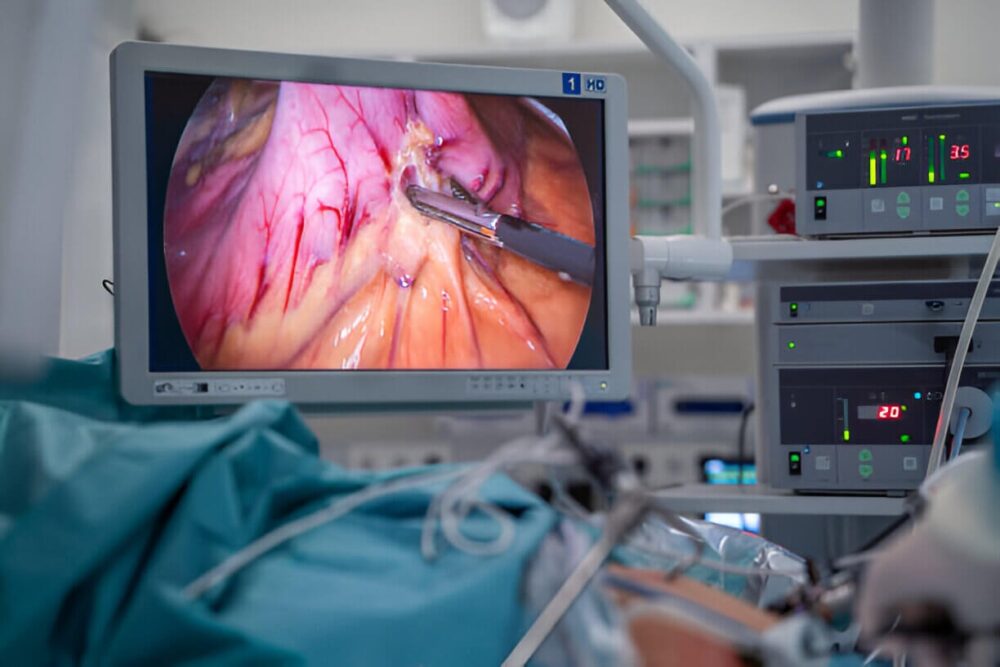

Colecistectomía Laparoscópica

Cirugía de vesícula biliar para el manejo de cálculos y enfermedades asociadas, con técnicas seguras que reducen el tiempo de hospitalización y aceleran la recuperación.

Técnica laparoscópica que reduce la capacidad del estómago, favoreciendo una pérdida de peso significativa y duradera.